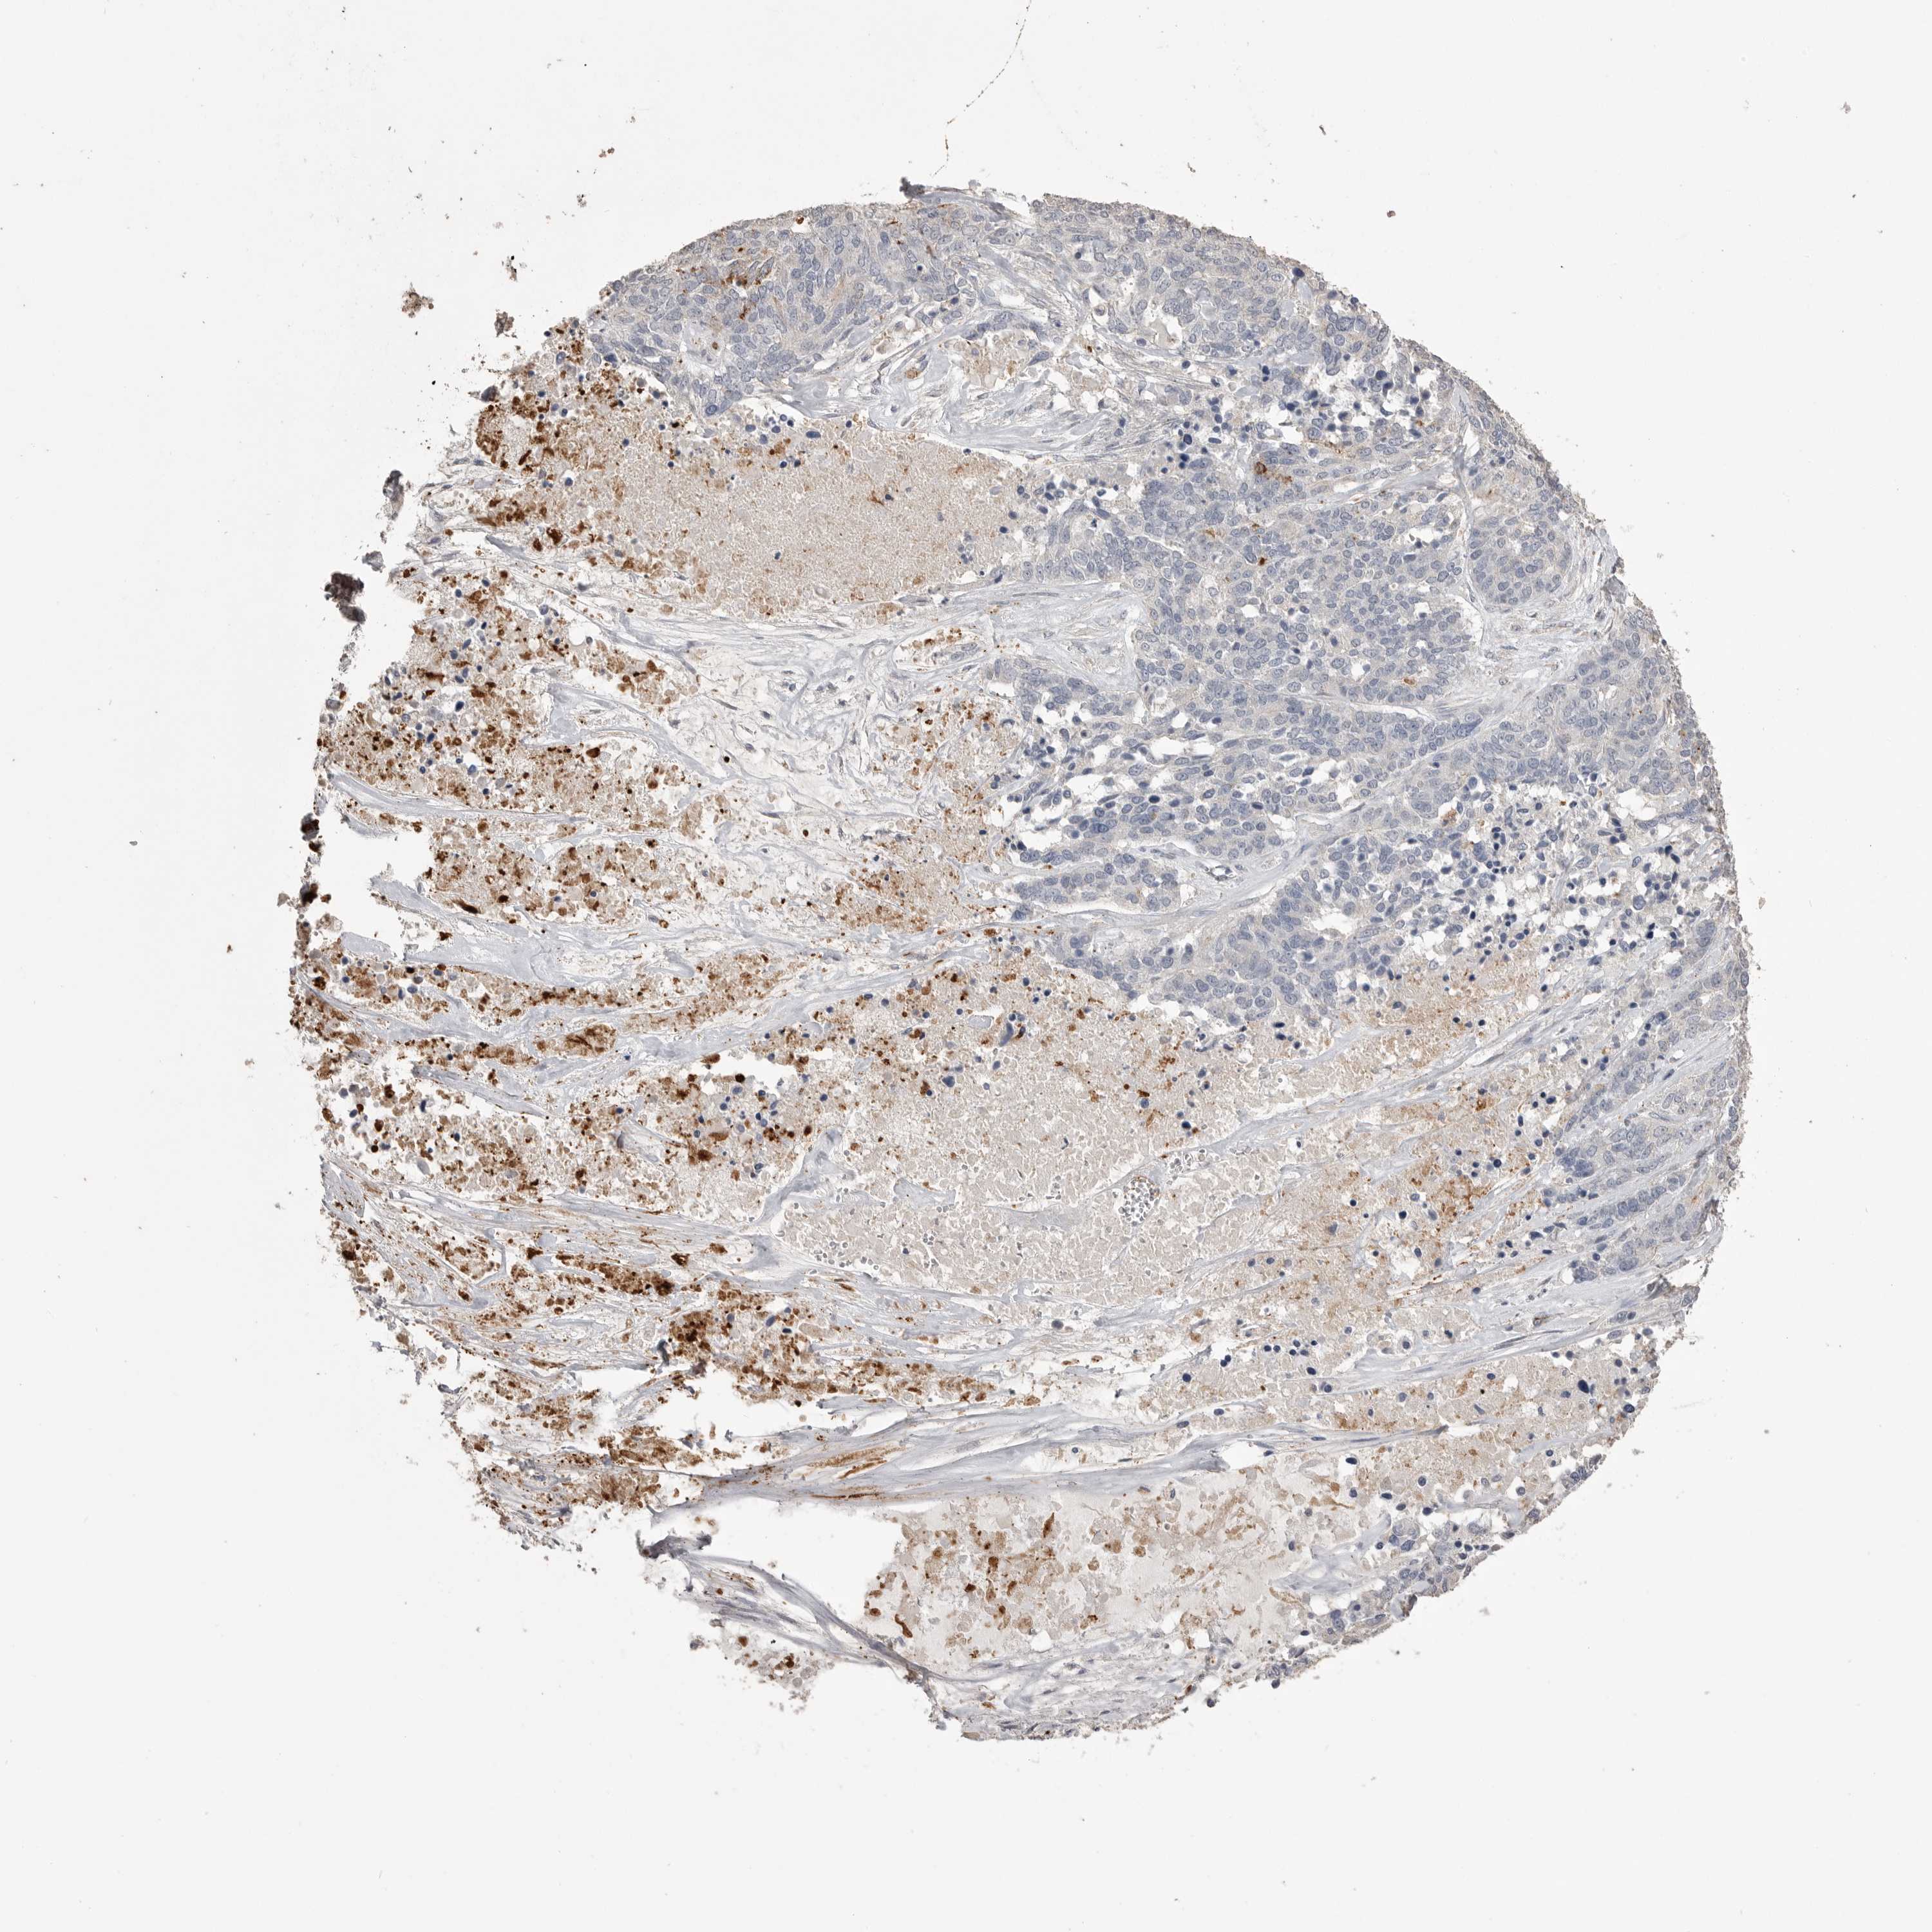

OVARIAN CANCER - Protein expressioni

A mouse-over function shows sample information and annotation data. Click on an image to view it in a full screen mode. Samples can be filtered based on level of antibody staining by selecting one or several of the following categories: high, medium, low and not detected. The assay and annotation is described here.

Note that samples used for immunohistochemistry by the Human Protein Atlas do not correspond to samples in the TCGA dataset.

Antibody stainingi

Antibody staining in the annotated cell types in the current human tissue is reported as not detected, low, medium, or high, based on conventional immunohistochemistry profiling in selected tissues. This score is based on the combination of the staining intensity and fraction of stained cells.

Each image is clickable and will lead to virtual microscopy that enables deeper exploration of all samples and also displays staining intensity scores, fraction scores and subcellular localization as well as patient and tissue information for each sample.

Antibody CAB025869

Staining

High

Medium

Low

Not detected

Intensity

Strong

Moderate

Weak

Negative

Quantity

>75%

75%-25%

<25%

None

Location

Nuclear

Cytoplasmic/membranous

Cytoplasmic/membranous,nuclear

Cystadenocarcinoma, serous, NOS

Carcinoma, endometroid

Cystadenocarcinoma, mucinous, NOS

Carcinoma, NOS